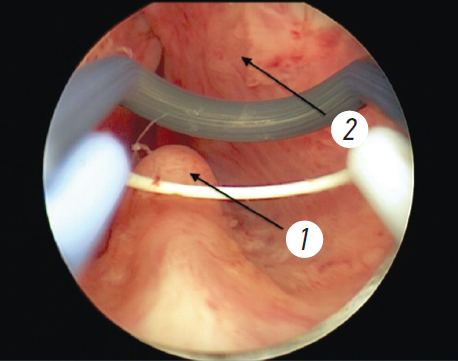

Хирургический этап лечения включал диагностическую уретроцистоскопию, позволяющую оценить состояние мочеиспускательного канала, шейки и слизистой оболочки мочевого пузыря, расположение устьев мочеточников, размеры предстательной железы (рис. 1). Следующим этапом было «вхождение в слой»: инцизия в области шейки мочевого пузыря до достижения волокон капсулы простаты с последующей энуклеацией аденоматозных узлов (рис. 2). Заключительный этап — морцелляция узлов гиперплазии. Все оперативные вмешательства проводили под спинальной анестезией.

Рис. 2. Этапы лазерной энуклеации предстательной железы: а — инцизия слизистой оболочки (1) позади семенного бугорка (2); b — диссекция ткани простаты (1 — аденоматозная ткань, 2 — капсула простаты)